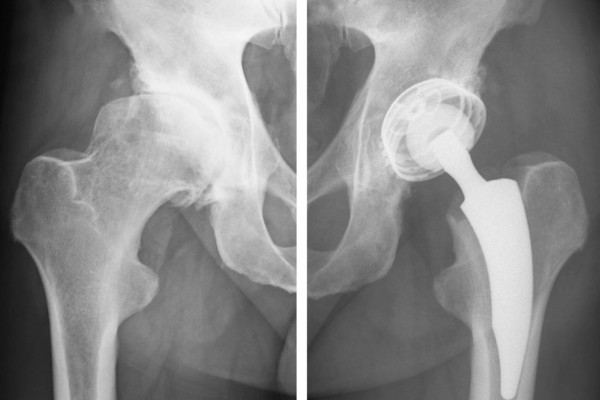

Ersatz des Schulter-, Knie- und Hüftgelenks (TEP)

Die 3 großen Gelenke des Körpers, die Schulter, das Knie und die Hüfte sind leider häufig durch Abnutzung oder nach Unfällen verschlissen. Wenn die konservativen Behandlungsmethoden nicht die gewünschte Linderung bringen, ist manchmal ein Gelenkersatz indiziert.

Dr. M. Matzer verwendet moderne, minimal invasive Techniken zur Implantation von Hüft und Knieprothesen.